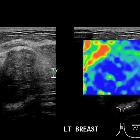

Breast ultrasound

Papilloma may be seen as a well-defined solid nodule or intraductal mass which may either fill a duct or be partially outlined by fluid - either within a duct or by forming a cyst. Color Doppler will demonstrate a vascular stalk.

A dilated duct can be frequently visible sonographically.